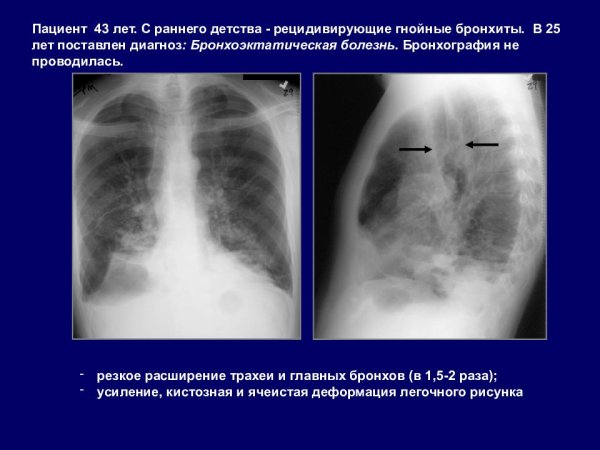

Деформация легочного рисунка - это состояние, при котором образование и распределение сосудистых и бронхиальных структур в легких претерпевает изменения. Это может быть следствием различных заболеваний, например, хронической обструктивной болезни легких (ХОБЛ), бронхоэктазов, фиброза легких или эмфиземы. Как результат, легочный рисунок становится нарушенным, что приводит к ограничению функции дыхания и возможному ухудшению общего состояния пациента. Для диагностики и оценки деформации легочного рисунка используются различные методы, такие как рентгенография грудной клетки, компьютерная томография или магнитно-резонансная томография. Лечение деформации легочного рисунка зависит от основного заболевания и может включать фармакотерапию, физиотерапию или хирургическое вмешательство.